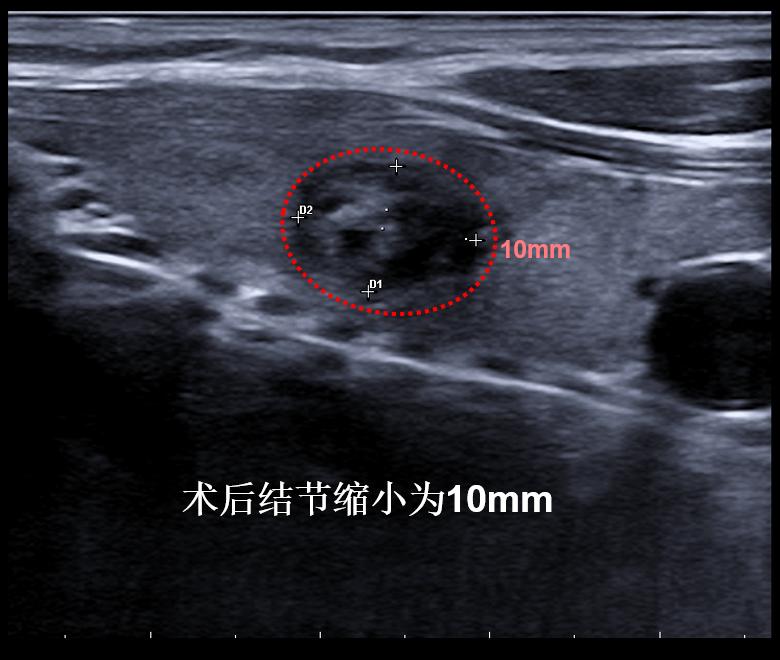

病例④: 3cm的甲状腺结节微创消融术后2月

微创消融前后超声对比,体积缩小99%